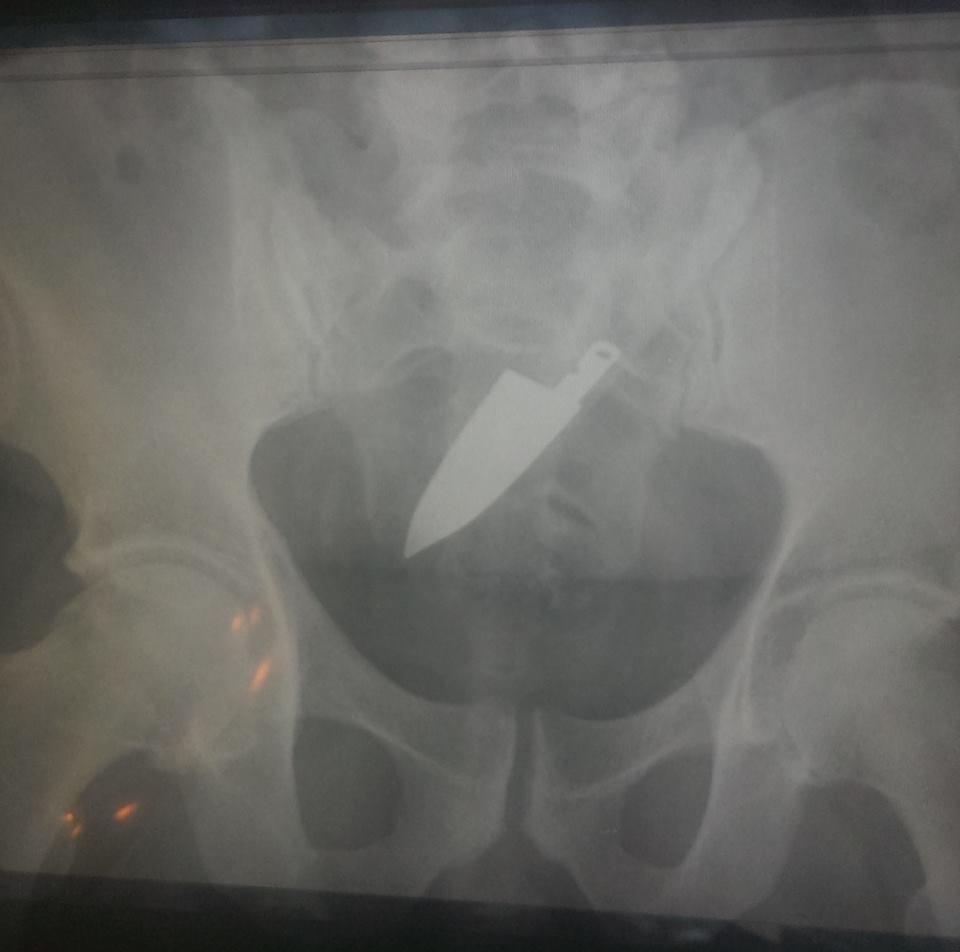

Faca:

Esse objeto sim deve ter dado um mega trabalho pra remover, como alguém pode engolir uma faca desse tamanho, que bizarro!